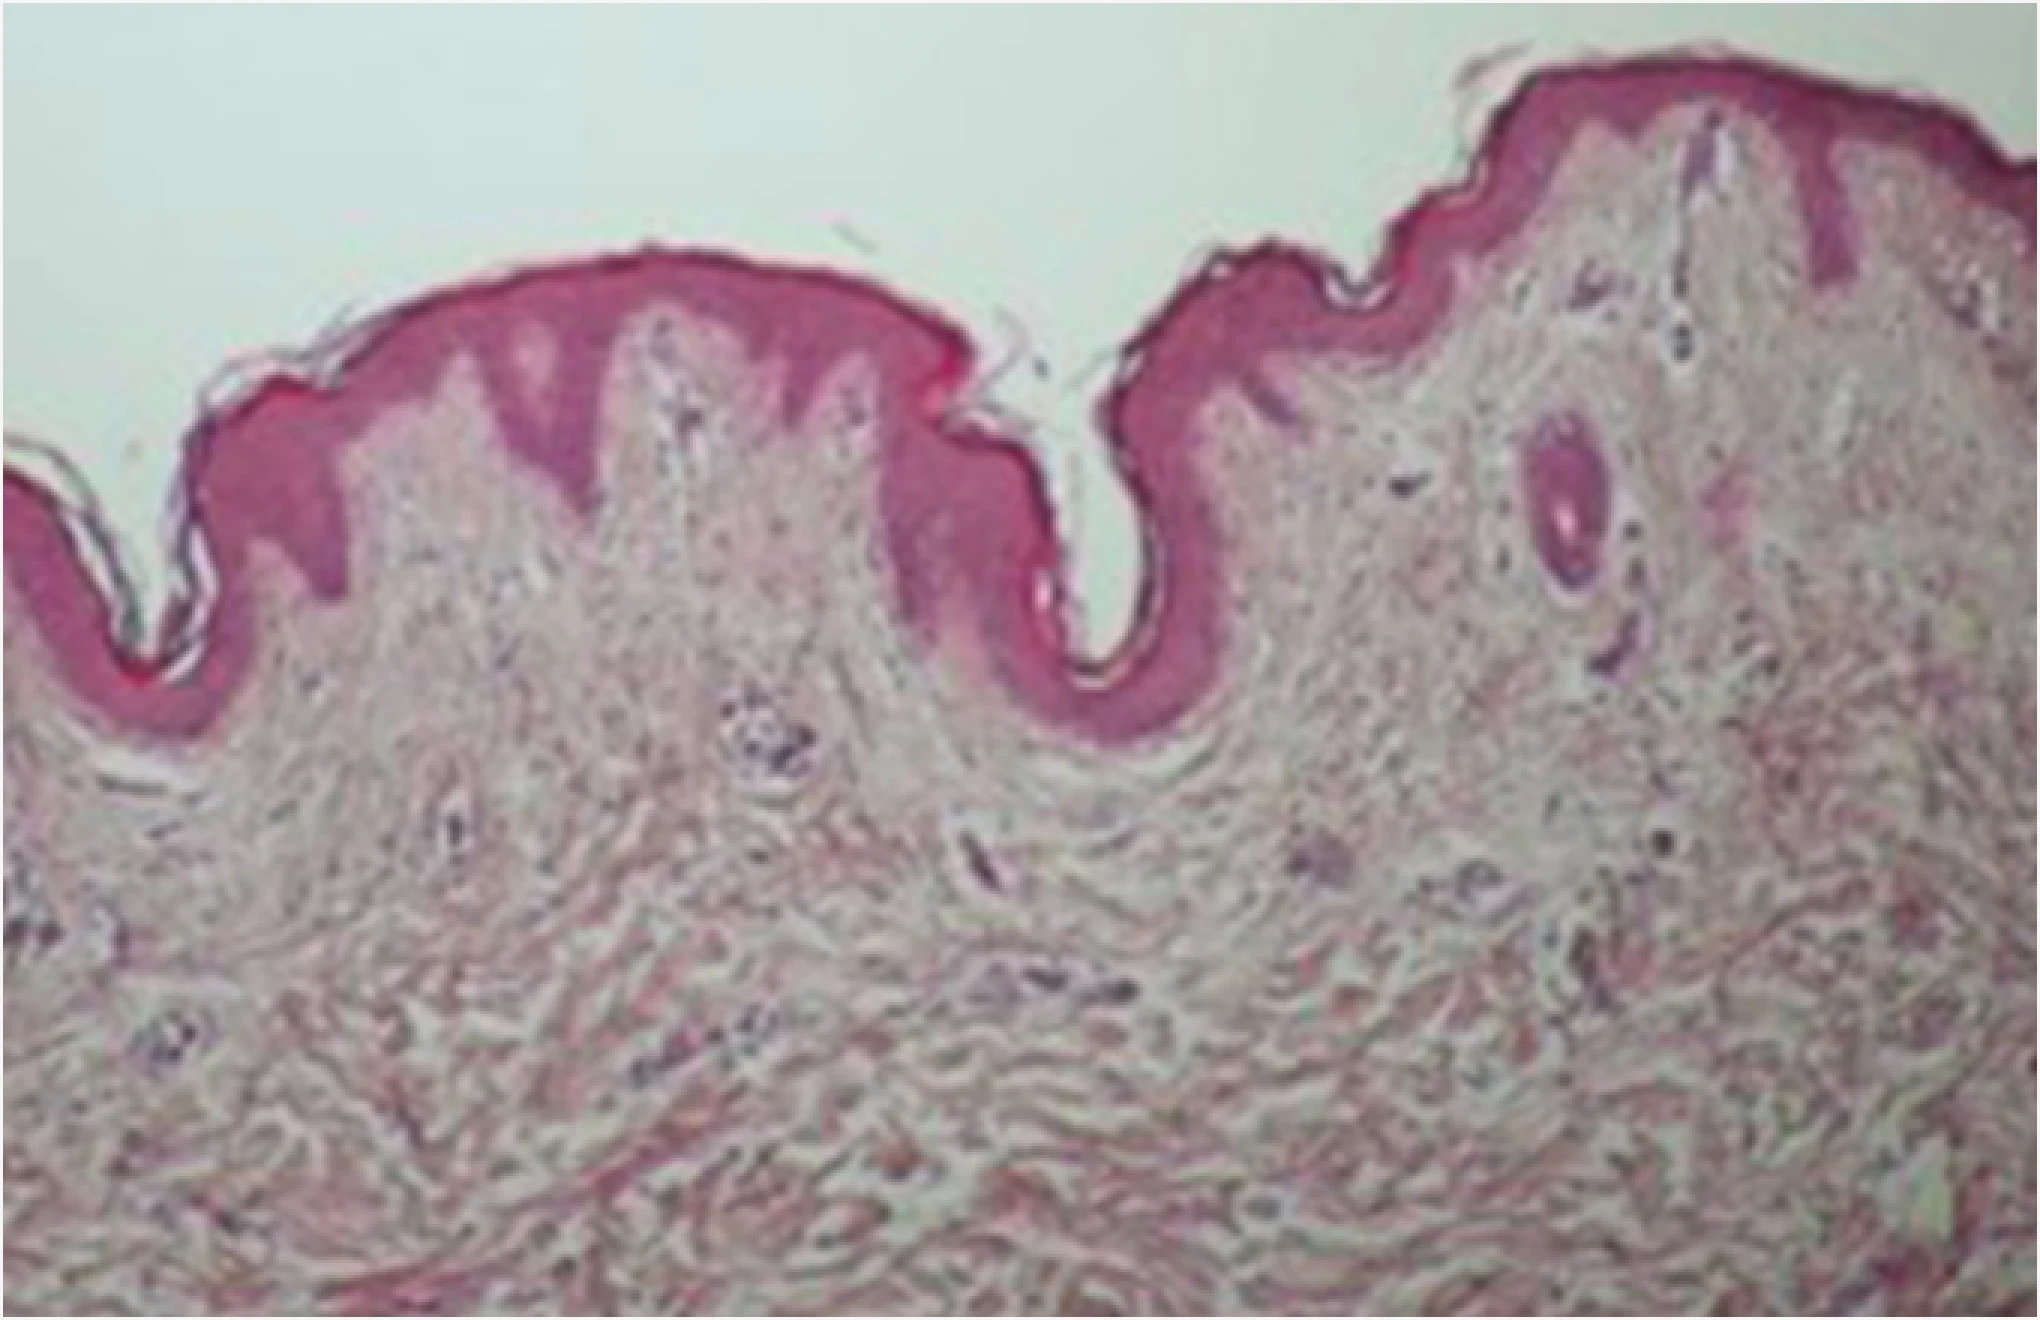

ONDA微波提升

ONDA治疗后,可以明显看到真皮层胶原蛋白被激活。

ONDA能量转化为热能,收缩松弛的胶原纤维并触发重塑

同时实现肌肤紧致与提升效果。

治疗前

治疗后